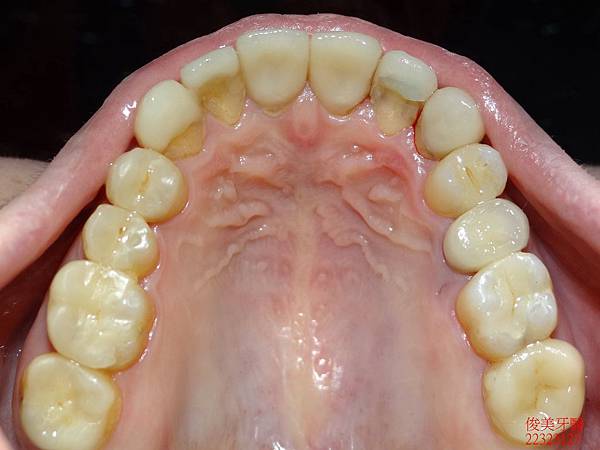

裝上新牙齒囉!!

其他的部份也做相同的處理。

最後將前牙的蛀牙及咬裂的部份一併修復,採用全瓷美白貼片一次到位,

兼具美觀及保護牙齒的神經喔!!牙齒也恢復為正常的牙弓形狀。

完美到一個不行........

療程結束後咬合良好。

牙縫不會直接嵌塞食物。

變身為超完美牙齒!!只能狂按"讚"啦~~~~~~~

患者非常滿意治療的效果。目前配戴維持器,定期檢查即可。